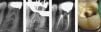

Para poder observar con claridad la tercera raíz son necesarias varias radiografías30,31. La obtención de una sola radiografía puede conducir con facilidad a errores de diagnóstico (fig. 2a). La colocación de una lima en la raíz adicional puede ofrecer el aspecto de una perforación13 (fig. 2b). Cuando los hallazgos radiográficos no son definitivos, la información que aportan los localizadores de ápice electrónicos nos permite hacer un diagnóstico diferencial y confirmar la presencia de conductos adicionales. Walker y Quackenbush26 llevaron a cabo un estudio y concluyeron que el simple análisis de radiografías de aleta de mordida permitía la detección de las raíces distolinguales en el 90% de los casos (fig. 3).

Tratamiento de conductos radiculares de un primer molar inferior con tres raíces. (a) Radiografía preoperatoria. (b) Radiografía de conductometría que muestra la curvatura apical de la lima en la raíz distolingual. (c) Radiografía postoperatoria. (d) Acceso modificado para permitir un abordaje en línea recta al conducto distolingual por debajo de la cúspide distolingual.

Carlsen y Alexandersen32 reseñaron el estudio de 398 molares inferiores permanentes con un complejo radicular y una raíz supernumeraria localizada lingualmente. Esta macroestructura, denominada radix entomolaris, presenta una elevada variación respecto al plano mesiodistal coronal. Cuando la posición de esta tercera raíz es vestibular, se denomina radix paramolaris. Solo dos publicaciones han descrito la presencia de una raíz adicional vestibular al principal conducto distal33,34. Su forma y curvatura son muy variables27,35,36 y puede variar desde la presentación de una corta extensión cónica hasta la presencia de una raíz completamente normal (fig. 2a–c). Lo más típico es que el eje de la raíz se enfrente a la cara vestibular del molar. Por ello, a la hora de medir la longitud del conducto radicular resulta más fácil seleccionar como punto de referencia la cúspide distovestibular que la cúspide distolingual que habitualmente se emplea (fig. 2d). La inclinación del orificio junto con la curvatura vestibular del tercio apical (fig. 4c) resultan en un conducto muy complejo de instrumentar e irrigar. Para evitar percances, cuando se trata la porción apical, es aconsejable escoger instrumentos pequeños y muy flexibles. La figura 4 muestra un primer molar inferior con tres raíces extraído como consecuencia de un fracaso endodóncico producido por perforación por desgaste (stripping) de la raíz distolingual (fig. 4d).

La localización del orificio requiere realizar modificaciones en las aperturas de acceso convencionales del primer molar inferior. Lo que está indicado es la extensión de la cavidad de acceso hacia el conducto distolingual para conseguir así un acceso en línea recta (figs. 2d a 4a). El tercio coronal del conducto presenta una aguda curvatura que debe tenerse en consideración para evitar perforaciones o desgastes (stripping) y evitar la eliminación de excesivas cantidades de dentina en la cara lingual del acceso radicular del conducto accesorio.